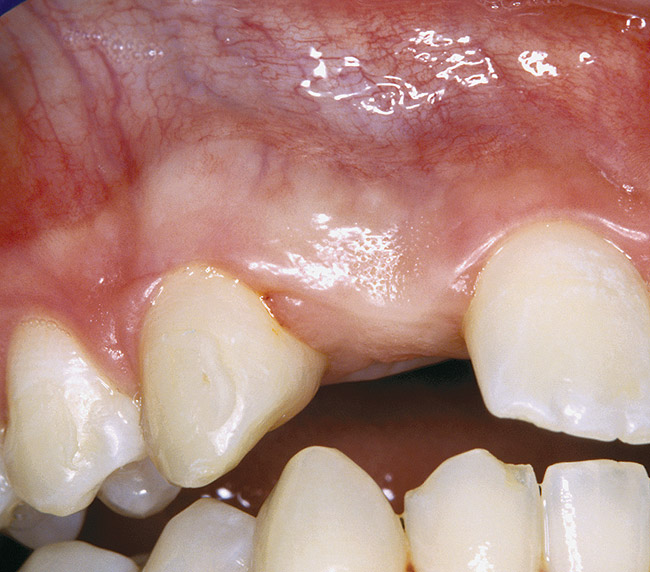

Figure 4  DIAGNOSTIC INFORMATION Significant crestal width of keratinized tissue, buccal view.

Figure 4

Periapical radiographs were taken to help determine the mesial-distal inclinations of the adjacent tooth roots (Figure 1). The radiographs revealed a serious issue, convergent roots for the right canine and right central, which eliminated that area as a potential implant-receptor site. The space between the left central and canine teeth was minimal, although the roots were relatively parallel. Clinical examination (manual palpation of the root eminences superiorly to the vestibule on the right side) confirmed the root convergence (Figure 2). The flat, wide zone of the keratinized tissue and lack of interdental papilla was evident for the missing right lateral incisor. There was a marked difference in clinical appearance for the left lateral, which could impact the eventual plan of treatment (Figure 3). Other significant clinical findings included bilateral facial bone concavities, which existed as a result of the congenitally missing tooth roots. As a diagnostic cue to the underlying bone topography, it is important to follow the demarcation between attached and unattached gingival tissue, and note the crestal width of the available keratinized tissue (Figure 4).